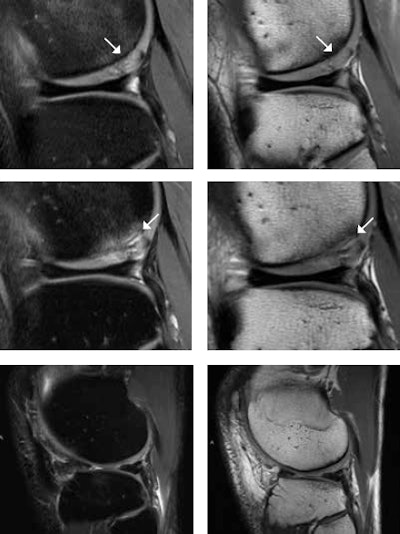

For instance, the interpretation of knee MRI examinations in New Zealand tends to focus on the differentiation between acute and chronic findings, and this is related to the insurance system. Every New Zealand resident is enrolled in the insurance system for accidents without any extra costs, but the insurance covers only the costs for the diagnosis and treatment that are related to a specific accident. Weidekamm explained that here is quite often a fine line between acute injuries and pre-existing disorders that result in osteoarthrosis -- e.g., related to anterior cruciate ligament deficiency or meniscus tears.

To develop skills in sports imaging, involvement in sporting events also can be valuable. In 2007, her group investigated the knees of Vienna city marathon runners, before and after the race.

"The teaching point was the direct collaboration with patients and their clinical findings and a better understanding of pre-existing findings on MRI that were related to their intense training prior to the run," she recalled. "It is crazy how much the athletes punish themselves and train through their pain. I understand that most of the athletes struggle with reducing their training program during the preparation for the race, though they have incredible pain."